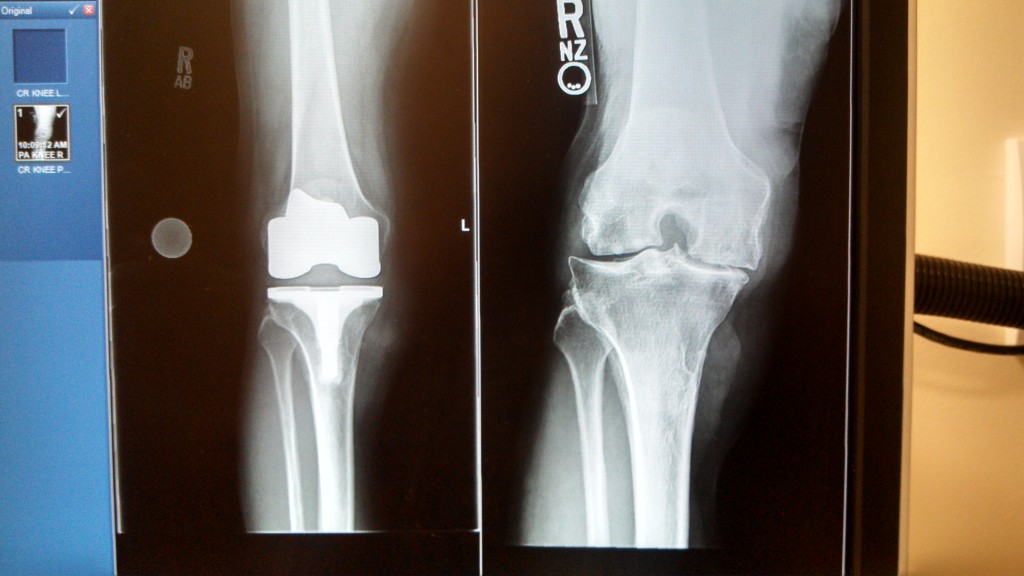

Knee Replacement

I had had multiple meniscus tears in my right knee as a result of increasing debilitation. My retirement plan included hiking in the Alps. Several surgeons I saw agreed I only needed right lateral unicondylar replacement and HSS was definitely the place to go. Thank you Dr. Peter Sculco!!! I completed the Tour du Mont Blanc without difficulty and was the only one not complaining of knee pain. The trip required hikes of 9-10 miles per day up and down 2500-4000 ft. Don’t be horrified Dr. Sculco - I feel great! I spent another 3 weeks hiking in Switzerland. Next year you will find me in the Italian Dolomites!